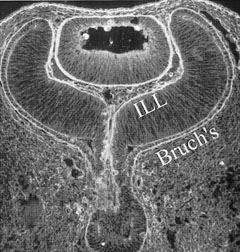

During invagination of the optic vesicle, the basal lamina of the surface ectoderm enters the invagination along with the ectodermal cells that have become specialized neural ectoderm.113The ectodermal cells that are on the surface of the inner with the outer basal lamina give rise to retinal pigment epithelium attached to Bruch's membrane, while the invaginating neural ectoderm and its basal lamina give rise to the neural retinal cells adherent to the internal limiting lamina (ILL). Thus, the basal laminae of both the retina and RPE have the same embryologic origin. Figure 5 demonstrates the continuity of these two basal laminae. It is important to appreciate that these basal laminae serve as interfaces between adjacent ocular structures. In the case of the ILL, this basal lamina is the interface between the retina and vitreous. Bruch's membrane separates the RPE and retina from the choroid (neural crest origin).

Fig. 5. Immunohistochemistry of posterior interfaces in the human embryo. This specimen, taken at about the 9-week stage of embryogenesis, was stained with an anti-ABA fluorescent marker that binds to extracellular components of the basal laminae. The continuity of the basal laminae destined to become the internal limiting lamina (ILL) and Bruch's membrane is evident. (Courtesy of Greg Hageman, PhD)

These interfaces play an important role in a significant biologic event that underlies one of the most devastating causes of blindness in humans: neovascularization. At the ILL interface between vitreous and retina, neovascularization in advanced diabetic retinopathy and other ischemic retinopathies, including retinopathy of prematurity (see below), is a significant cause of vision loss. At the level of Bruch's membrane, an interface of identical embryologic origin as the ILL, neovascularization in age-related macular degeneration is a significant and growing problem. Both of these conditions result from vascular endothelial cell migration and proliferation onto and into interfaces of the same embryologic origin: the basal lamina of the surface ectoderm. Improving our understanding of endothelial cell interaction with these interfaces should provide new insights into therapy and prevention of these important disorders.